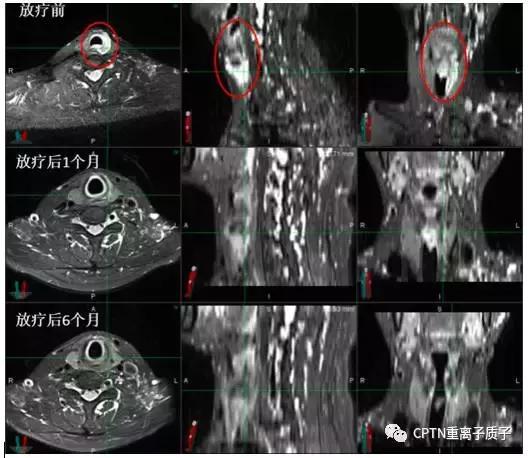

气管腺样囊性癌患者一例。肿瘤生长在上段气管内,如手术则无法保留喉发声的功能。经过重离子根治性放疗,放疗结束后1个月肿瘤就几乎完全消失,目前已无瘤生存超过6个月。治疗仅造成轻度声音嘶哑、食管炎和皮肤反应,且上述反应在治疗后1月几乎完全消失。

图为高危局限期前列腺癌患者,初诊 PSA最高达21.359ng/ml。既往有高血压、冠心病等内科基础疾病,手术风险大,后行根治性重离子治疗联合内分泌治 疗。治疗结束后复查PSA:0.221ng/ml,复查MRI提示前列腺肿瘤从治疗前2.1*1.9cm缩小到0.8*0.8cm(如图所示,红色圆圈部分)。治疗后半年随访PSA:<0.003ng/ml,治疗及随访过程中未出现尿*禁失**、排尿困难等并发症,可以正常参加各类社会活动。